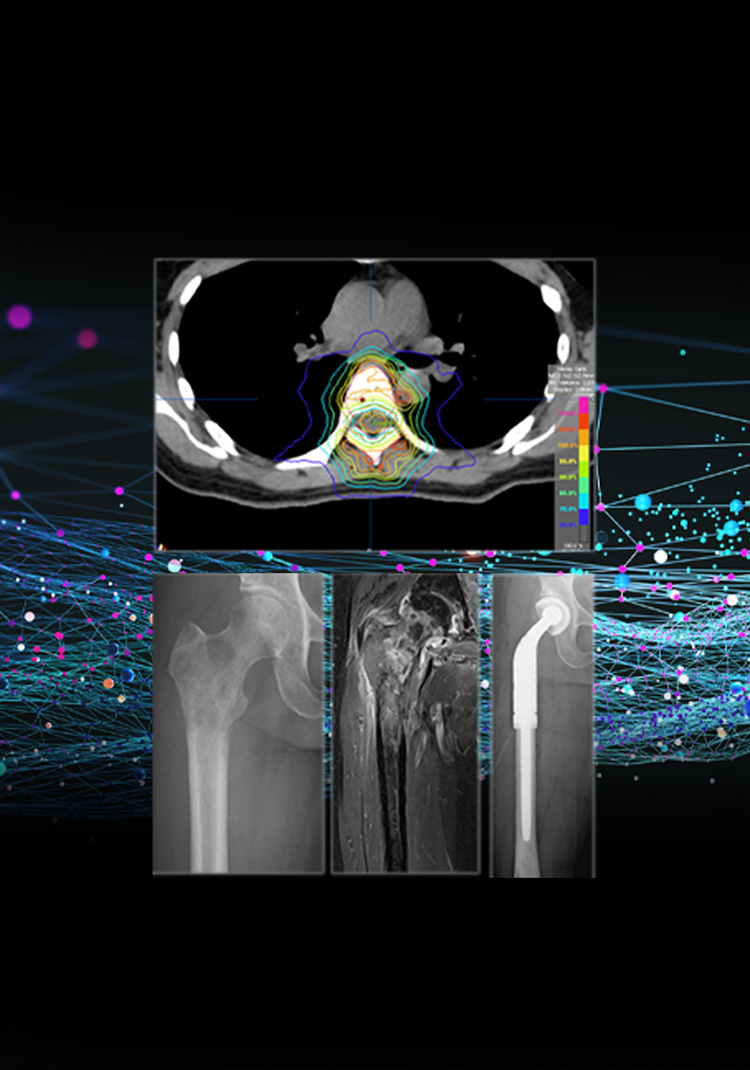

がんになっても痛みなく

動けるように

骨転移を集学的に診療し

生活の質の改善を

目指します